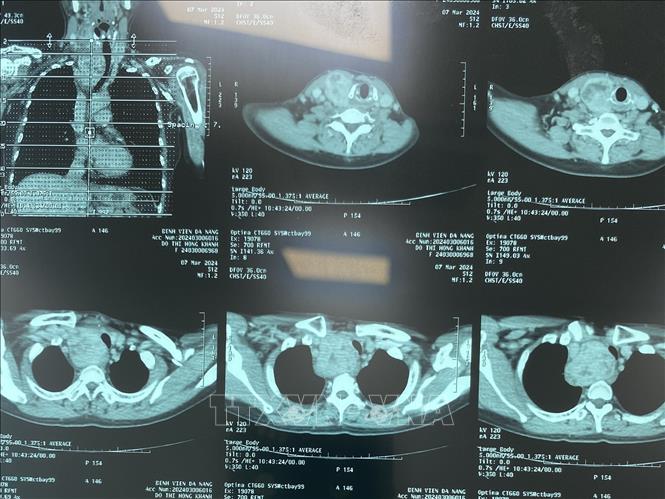

Chẩn đoán hình ảnh X quang.

Trước đây, việc in phim đối với các dịch vụ chẩn đoán hình ảnh như chụp X-quang, chụp cắt lớp vi tính (CT) và chụp cộng hưởng từ (MRI),… nhằm cung cấp kết quả chẩn đoán dưới dạng vật lý, phục vụ công tác khám bệnh, điều trị, hội chẩn, chuyển tuyến, lưu trữ hồ sơ bệnh án và đáp ứng các yêu cầu về giám định, pháp lý.